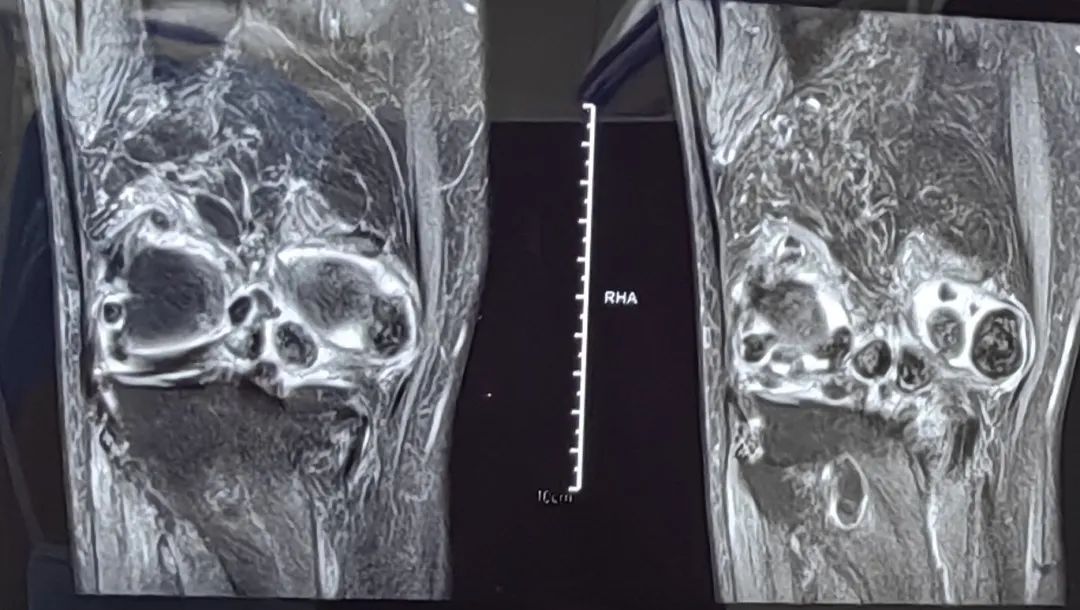

近日,我院骨科团队为一位78岁腘窝滑膜软骨瘤病女性患者进行了关节镜微创手术。由于病变位于腘窝,早期不影响膝关节活动,疼痛症状时轻时重,加上对开放手术的恐惧,患者竟然坚持了近40年,直到术前患者膝关节屈伸活动受限,患膝肿胀明显,因疼痛不敢负重走路,才下决心来院手术。

滑膜软骨瘤病病因不明确,好发于具有滑膜组织的关节囊或腱鞘内,多数学者认为滑膜软骨瘤病是一种滑膜化生性疾病,少数学者认为,该病变性质介于良性的内生软骨瘤与恶性的软骨肉瘤之间,滑膜软骨瘤病根据滑膜化生学说分为原发型和继发型两大类;原发型指的是以胚胎学说为主,即残存胚胎组织活化、增生,引起滑膜化生。继发型指的是炎症、外伤等因素刺激关节滑膜化生引起关节内游离体形成。滑膜骨软骨瘤病进展形成游离体后,会引起关节绞索,疼痛等症状,这时就需要进行手术干预,以减轻对关节的进一步损伤,改善患者的生活质量。